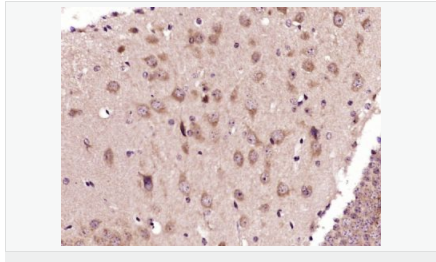

| 產(chǎn)品應(yīng)用 | WB=1:500-2000 IHC-P=1:100-500 IHC-F=1:100-500 Flow-Cyt=3ug/test ICC=1:100-500 IF=1:100-500 (石蠟切片需做抗原修復(fù)) not yet tested in other applications. optimal dilutions/concentrations should be determined by the end user. |

| 產(chǎn)品介紹 | This gene encodes an adenosine receptor that is a member of the G protein-coupled receptor superfamily. This integral membrane protein stimulates adenylate cyclase activity in the presence of adenosine. This protein also interacts with netrin-1, which is involved in axon elongation. The gene is located near the Smith-Magenis syndrome region on chromosome 17. [provided by RefSeq, Jul 2008]. Function: Receptor for adenosine. The activity of this receptor is mediated by G proteins which activate adenylyl cyclase. Subcellular Location: Cell membrane; Multi-pass membrane protein. Similarity: Belongs to the G-protein coupled receptor 1 family. SWISS: P29275 Gene ID: 136 Database links: Entrez Gene: 136 Human Omim: 600446 Human SwissProt: P29275 Human Unigene: 167046 Human Important Note: This product as supplied is intended for research use only, not for use in human, therapeutic or diagnostic applications. |